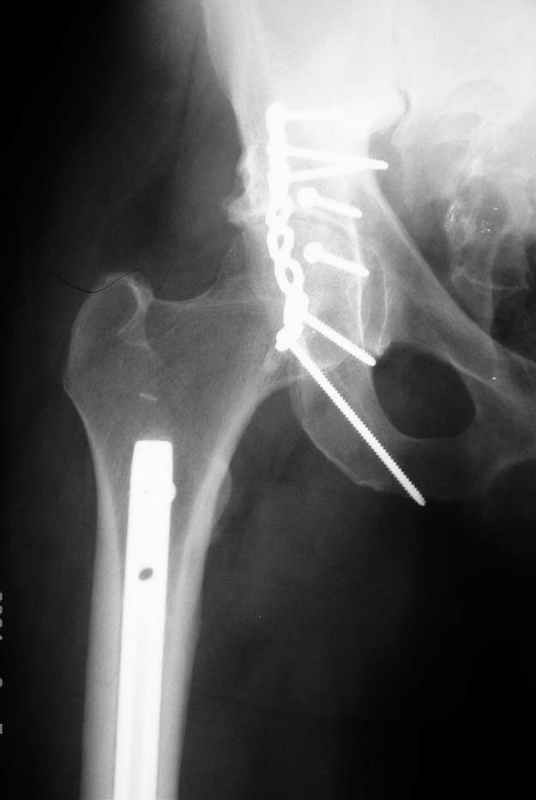

Не дождавшись советов, в понедельник прооперировал больного, заняло времени..., но все сделал в один этап: сначала фиксировал ипсилатеральный перелом бедра и шейки реконструктивным гвоздем Smith&Nephews, потом из расширенного илеофеморального доступа фиксировал перелом крыла подвздошной кости тягловым винтом, нейтрализующей пластиной заднюю колонну, и тягловыми винтами 3,5 мм переднюю колонну.

перелом крыла правой подвздошной кости, перелом обеих колонн вертлужной впадины, двусторонний перелом лонных костей (С2.2) повреждение передних связок правого крестцово-подвздошного сочленения,

ипсилатеральный перелом шейки и диафиза бедра.

К сожалению, набора для ретроградного или антеградного реконструктивного штифтования в операционной нет, поэтому доставка заняла н-ное время. Вопрос, который возник у меня- по поводу оптимальной тактики хирургии: вся фиксация в один этап из расширенного доступа или последовательно сначала бедро и позже реконструкция впадины, комбинированный доступ к впадине отдельно к передней и задней колоннам или из расширенного илеофеморального одного доступа. Все-таки решил остановиться на одноэтапном подходе и спустя 5 дней (как раз и наборы привезли) из расширенного илеофеморального доступа сначала фиксировал реконструктивным штифтом Smith&Nephews бедро и

шейку (благо перелом шейки 2 типа -относительно стабильный) затем фрагмент крыла подвздошной кости Lag screw, далее пластина на заднюю колонну и винты в переднюю колонну.(с размерами и направлением винтов ошибка вышла:-((, но интраоперационно у меня была полная уверенность , что винты *ушли* в лонную кость).